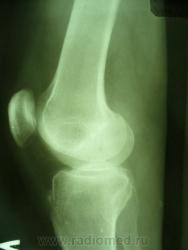

Уважаемые коллеги. Не так давно на странице сайта обсуждалась тема гипердиагностики ДОА. Хотелось бы увидеть ваше мнение по поводу наличия/отсутствия ДОА на представленных снимках. Лет 8 назад попал в автодорожку где-то в другом регионе, там же лечился в НИИТО (со слов, т.к. документов никаких нет) и там же наблюдался с DS: ДОА правого к/с IIст. Переехал в наш регион и решил пройти МСЭК для получения группы инвалидности. Снимки перевернуты, чтобы скрыть маркировку. Так есть ли ДОА?

Латерализация обоих надколенников, мелкий остеофит по верхнему краю правого надколенника, вытянутость и заострение межмыщелковых отростков левой б/б кости.

Вот что хотелось бы уточнить---а что это у нас с межмыщелковыми возвышениями справа???? а что это за окостенение по наружному контуру латерального мыщелка бедра??? ТРАВМА В АНАМНЕЗЕ!!!! Так что - справа - норма? Извините - не уверен. Група не только по снимкам определяется...функция тоже учитывается. А если сделать пару снимков для оценки межмыщелкового углубления и этих самых возвышений.

Выбирай, не выбирай..., а получается только гетерогенное окостенение у внутреннего надмыщелка правой бедренной кости. А с инвалидностью? Косинская как раз и работала в Ленинградском институте экспертизы трудоспособности инвалидов: 2 ст. = 2гр., 3 ст. = 1 гр., в данном случае - никакой группы. Молодцы травматологи, вылечили человека в НИИТОУлыбаюсь!

А почему так явно сточены межмыщелковые возвышения справа,  и вопрос: раз рядом с коленом палец - значить его придерживали, или может вообще фиксировали, как палец оказался на снимке? Последнее могло повлиять на рентген картину.

Все правильно замечено. Это, конечно не пальцы, а дополнительные фрагменты костной структуры. Была травма, больной лечился в ИТО. Вероятно, это окостеневшие фрагменты связок, хряща или чего там еще. И межмыщелковое возвышение "изгрызано", м.б. был перелом верхушек. Но ведь это все это не является R- признаками ДОА. Цель демонстрации - выяснить, есть ли рентгеновcкие признаки обезображивающего остеоартроза?